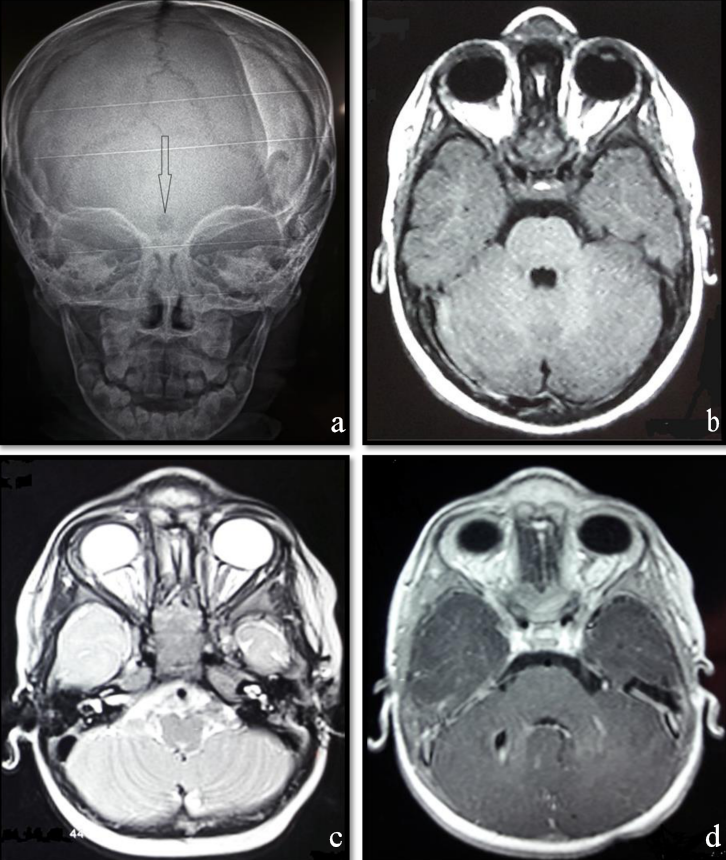

An 18-month-old infant without specific pathological history presented at 1 month of admission a median frontal swelling facing the nasion associated with a citrin yellow flow of increasing intensity without fever. Clinical examination showed a nasofrontal fistula allowing a flow to the top of a small inflammatory mass slightly sensitive to palpation (Figure 1 [Fig. 1]) evolving in a context of apyrexia and conservation of the general state. The frontal standard radiography of the skull showed a medial frontal bone defect (Figure 2a [Fig. 2]). Magnetic resonance imaging (MRI) of the brain (Figure 2b–d [Fig. 2]) demonstrated a median basifrontal cystic lesion in favor of a fistula associated with a nasofrontal cyst, which appears hypointense on T1 (Figure 2b [Fig. 2]) and hyperintense on T2 (Figure 2c [Fig. 2]) and enhances after gadolinium injection (Figure 2d [Fig. 2]), underlining that the infectious assessment was normal. The patient was operated by performing a small, median nasofrontal incision centered on the mass (Figure 3a [Fig. 3]), careful dissection around the cyst (Figure 3b [Fig. 3]), and its complete removal (Figure 3c [Fig. 3]). The defect of the dura mater (Figure 4a [Fig. 4]) was closed by making hermetic sutures, and the bone defect was clogged by a small flap of the external table taken from the frontal bone in precoronal (Figure 4a–b [Fig. 4]). The incision was esthetically closed by continuous absorbable intradermal sutures. The postoperative follow-up was simple without any incidents with excellent healing of the wound. Histological examination confirmed the diagnosis of the dermoid cyst and we report a very satisfying aesthetic result obtained 10 months after the surgical intervention (Figure 5 [Fig. 5]).

Figure 2: Frontal radiograph of the skull (a) showing nasofrontal bone defect and axial brain MRI weighted sequences T1 (b), T2 (c), and T1 contrast enhanced (d). The lesion sits in the medial basifrontal and appears hypointense on T1 and hyperintense on T2 sequences, and enhances after injection of the contrast product (d).